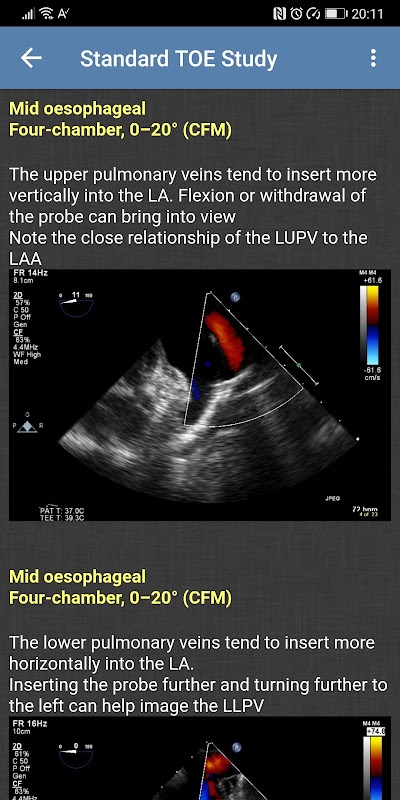

- Kajian TOE Standard